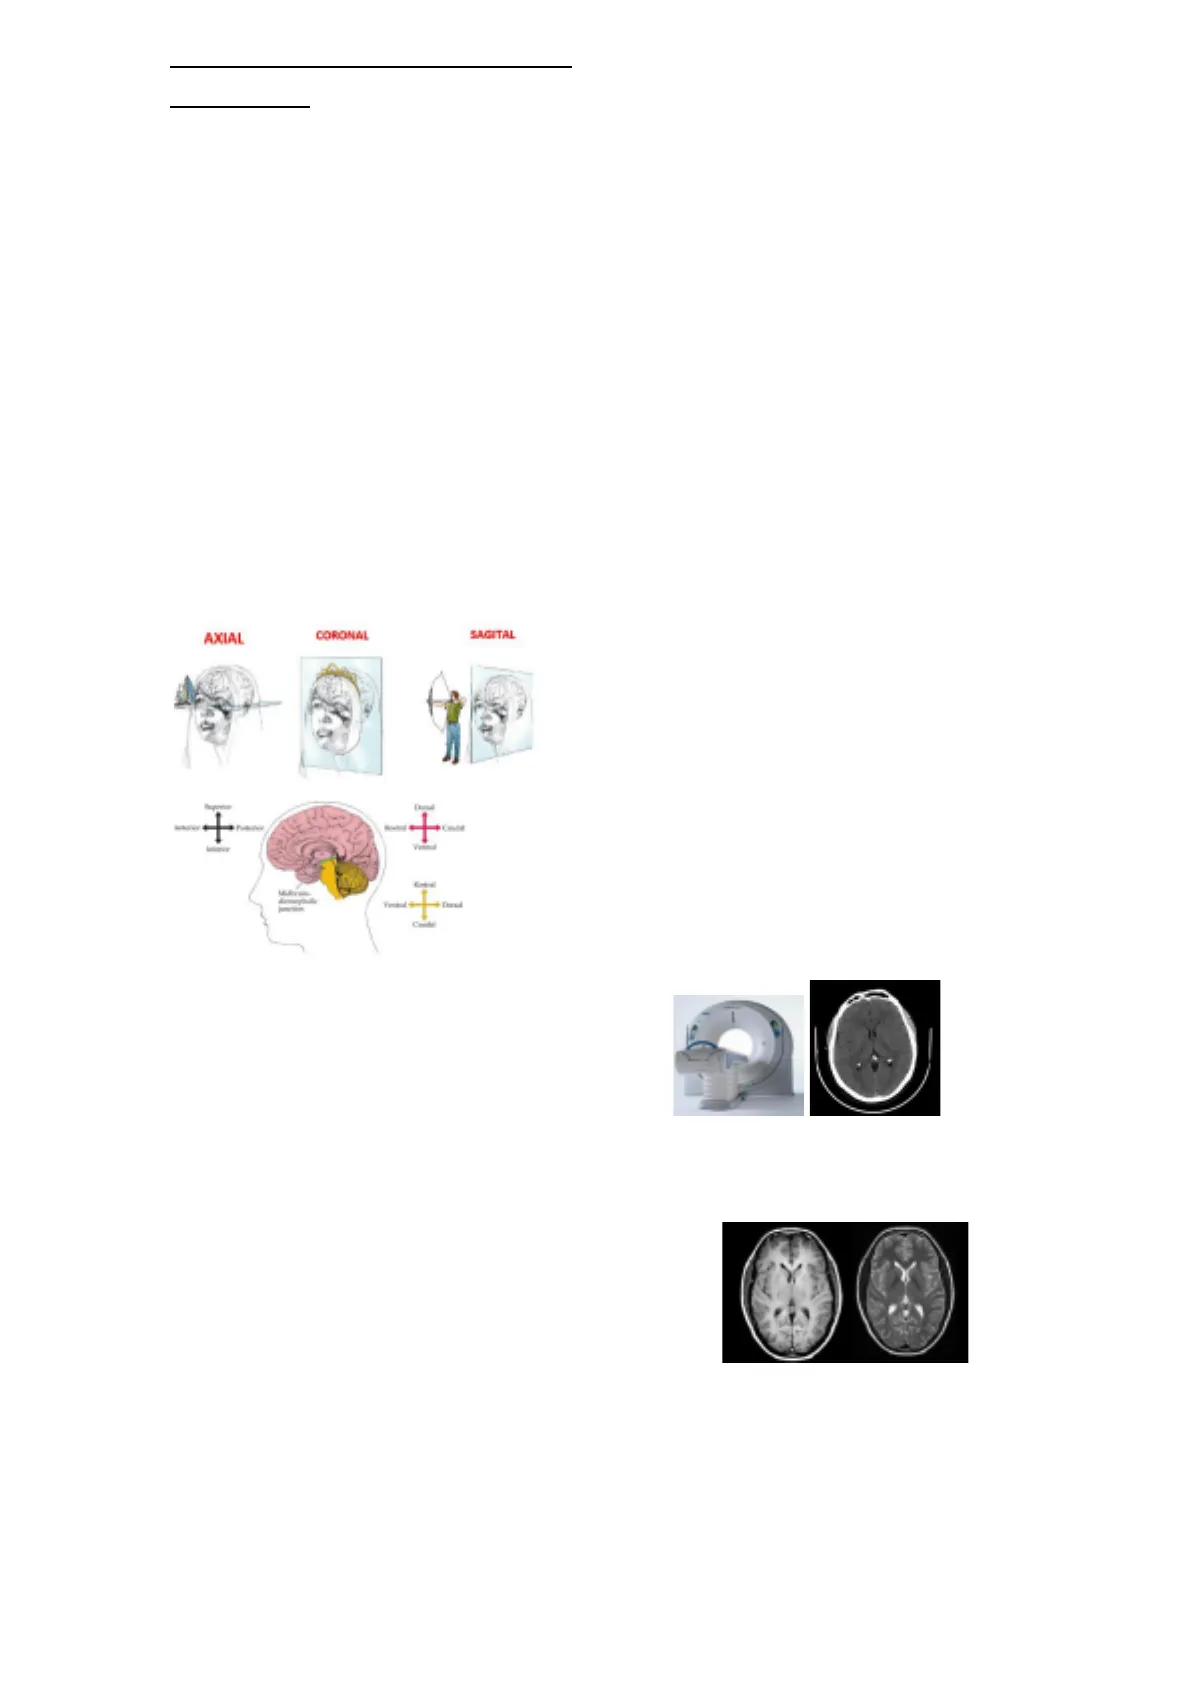

Tomografía

computerizada (TC):

o Abierto.

o Suelen ser casos urgentes.

o Rápido.

o Se ven muy bien zonas con hemorragias.

o TAC: tomografía axial computerizada: clásicamente

el escáner hacia solo cortes axiales.

o Blanco: hueso.

o Negro: agua de los ventrículos.

o Es importante observar la simetría.

o Lo blanco del centro son los plexos coroideos

calcificados.

Resonancia magnética (RM):

o Cerrada.

o Programada.

o Lleva tiempo.

o Detallada, compleja.

o Hay varias secuencias, las más básicas son T1 y T2;

una es inversa a la otra.

o T1: se parece más al escáner; el agua se ve negra.

o T2: el agua de los ventrículos se ve blanca.

T1 T2